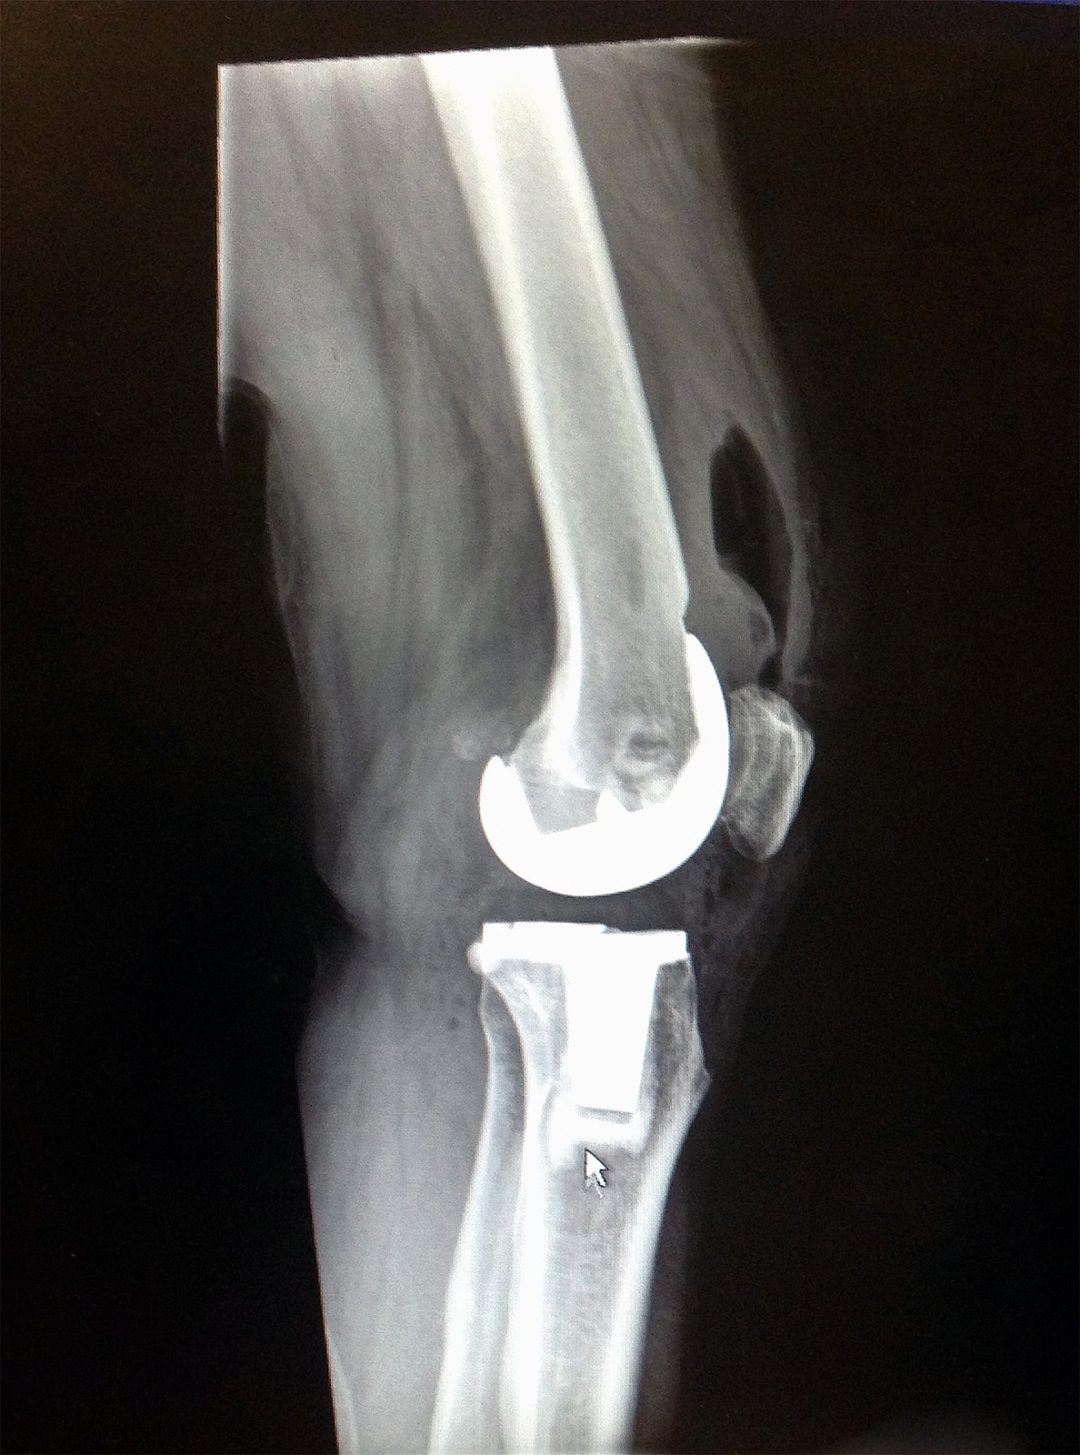

What a new knee looks like when it is all over. Credit: Bob Nesoff